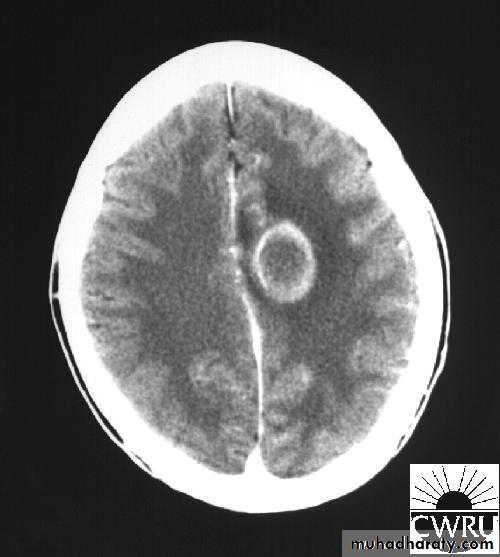

Brain Abscess CT without contrast

Brain Abscess CT with contrast

• B. Radiological Investigations:• CT or MRI is the investigation of choice.

• CT Brain is performed with and without contrast.

• MRI is done with gadolinium enhancement.

• They will show a single (or multiple) space occupying lesion that is well delineated with an enhancing wall, with variable surrounding oedema.